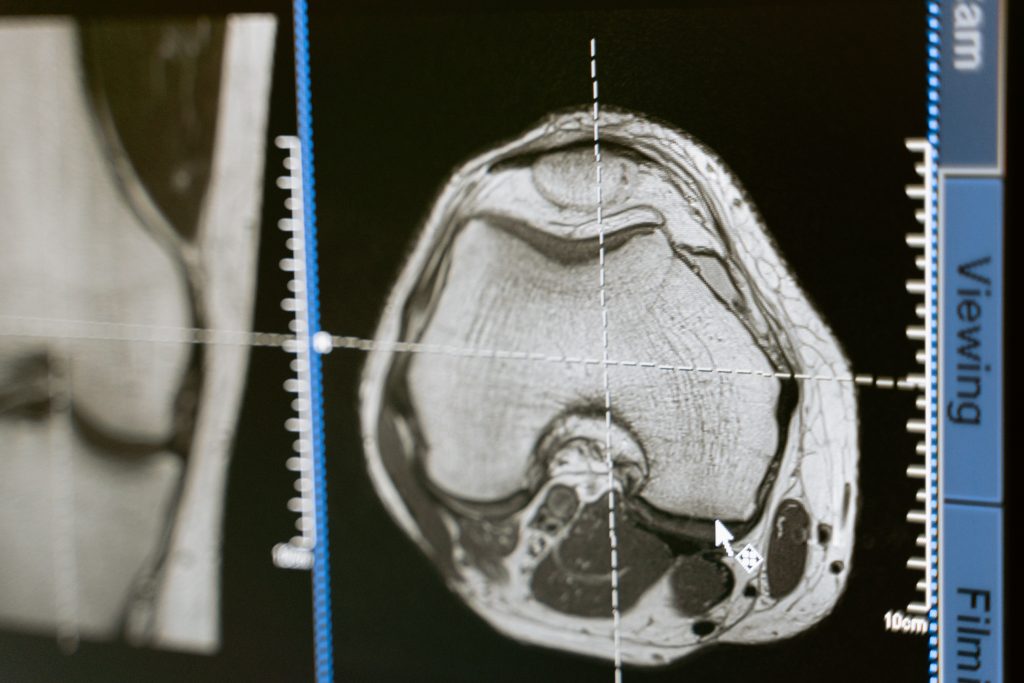

Pesquisadores da Fiocruz, da UFRJ, no Rio, e da Escola de Medicina Albert Einstein e da Universidade de Nova York, nos EUA, decidiram acompanhar o caso recente. Queriam traçar paralelos. O trabalho é fruto da tese de doutorado de Pedro de Freitas, sob orientação do professor Renato Rozental, pesquisador da UFRJ e da Fiocruz. A pesquisa contou com recursos não disponíveis na época do acidente do americano: exames como tomografia, eletroencefalograma, ressonância magnética, modulação da atividade elétrica cerebral e exames neuropsicológicos para avaliar as disfunções no lobo frontal e estimar as consequências da lesão.

No caso do brasileiro, já logo depois do acidente, os pesquisadores constataram que o seu lobo frontal esquerdo começou a compensar o lado lesionado. Isso ocorria desde que aquele lado não fosse recrutado para outra atividade. As diferentes áreas do cérebro se comunicam por meio de impulsos elétricos. Quando uma área é lesionada, a atividade elétrica começa a funcionar mal e essa comunicação cerebral interna piora muito. Entretanto, explica Rozental, o hemisfério sadio começa a compensar essa atividade.